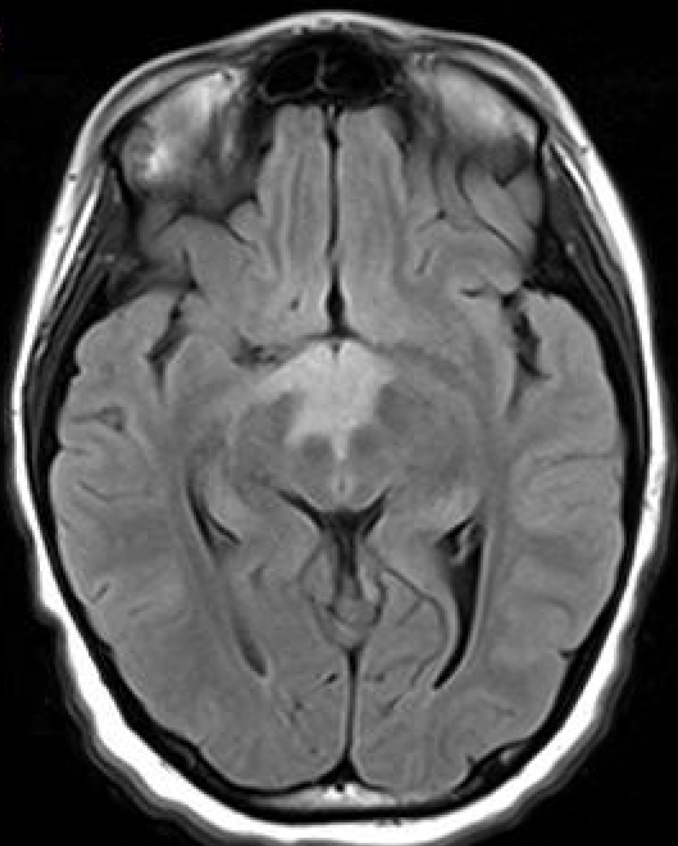

Case Presentation: 12-year-old girl presented with altered mental status, hypothermia, and bradycardia following one week of abdominal pain, progressive fatigue and flattened affect. Family denied ingestion, fever, cardiorespiratory symptoms, headaches or unusual exposures. Exam significant for Temperature 33.2 C, Heart Rate 42 bpm, sluggishly reactive pupils, disconjugate gaze, able to intermittently follow commands and localize to pain. Laboratory studies revealed hyponatremia, hypokalemia and negative infectious work-up. CSF analysis had a persistent lymphocytic pleocytosis and oligoclonal bands. MRI Brain showed a non-enhancing, ill-defined lesion involving the hypothalamus and majority of the diencephalon, eventually with scattered grey-matter lesions which showed hypercellularity on biopsy. NMO/AQP4 titer was positive in the CSF, but not the serum. She was diagnosed with probable Neuromyelitis optica (NMO) autoimmune encephalitis with predominantly hypothalamic involvement. IVIG had no effect. Steroid treatment provided minimal improvement. Rituximab resulted in near-resolution of symptoms.

Conclusions: As in this case, AE should be suspected in patients with an acute or subacute onset of neurologic symptoms that correlate with signs of inflammation on CSF studies, histopathological tests, and/or imaging. Other etiologies including toxins, vasculitis, metabolic and infectious should be explored. Though there is often diffuse brain involvement, presentations may have specific symptoms related to the localization of the initial inflammatory process. Hypothalamic involvement is reported to be associated with NMO/AQP-4 antibody-mediated encephalitis, though this patient lacked other typical symptoms associated with neuromyelitis optica (NMO). A history of autoimmune conditions as well as a preceding infectious prodrome support the diagnosis. Immunomodulatory therapy should be initiated as soon as infectious etiologies have been excluded to minimize morbidity and mortality. Clinical response should guide therapy, though treatment may take days-to-weeks to take effect and overall improvement in AE is often slow.